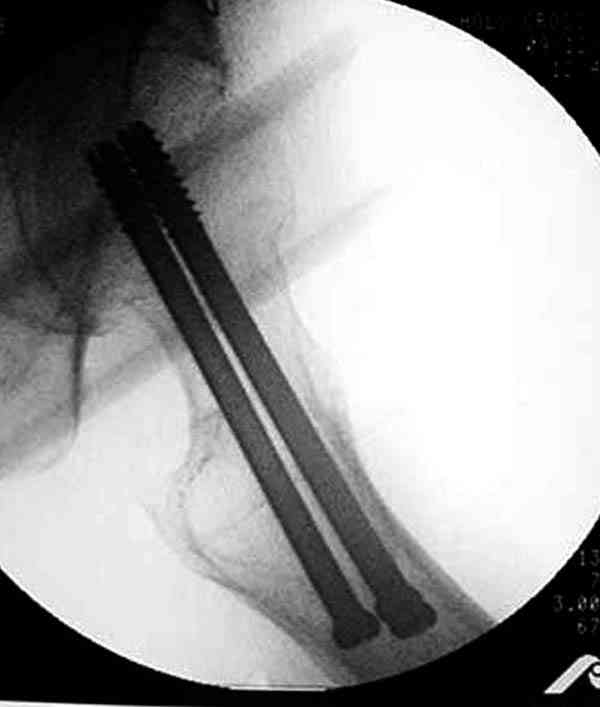

На Московской конференции в ноябре была продемонстрирована удивительная методика профилактического армирования шейки бедра у пациенток с остеопорозом и переломом контрлатеральной шейки в анамнезе.Странно, но дискуссии это сообщение не вызвало.Кто что думает об этом?

Спасибо, Антон. Я автор того сообщения по профилактическому армированию шейки бедренной кости, которое прозвучало на конференции, посвященной 50-летию создания АО. Мне тоже хотелось услышать вопросы по теме. Мы травматологи-ортопеды в первую очередь хирурги, а не терапевты. Почему в вопросе профилактики и лечения остеопороза мы ограничиваемся только консервативными методами лечения? Как можно практически научить больного не получать травмы, когда немало случаев возникновения переломов даже в постели. Первоначально идея армирования ШБК многих, при ком я озвучивал ее, шокировала, затем возникала дискуссия и большинство поддерживали эту идею. Мне бы очень хотелось развернуть дискуссию на странице этого сайта.

Кликните для загрузки файла P3230006.JPG

54KB (56062 bytes)

Уважаемый Антон! У меня было всего три клинических наблюдения, снимки были продемонстрированы на московской конференции. Количества этих снимков хватило для подачи заявки, а затем и получения патента на изобретение. В свое время РОСПАТЕНТ потребовал подтверждения методики клиническими наблюдениями. У одной из больных действительно произошла повторная травма, и произошел подвертельный перелом на стороне армированной шейки бедренной кости (см. снимки). Это подтвердило основную идею изобретения - была сохранена и головка, и армированная шейка бедренной кости. Но тут не обошлось безпроблем. Анестезиологи отказались давать наркоз, а провести остеосинтез под м/а пластиной и винтом DHS не согласилась больная. Дальнейшее лечение скелетным вытяжением. На контр. Рентгенограмме через 2 месяца признаки формирования костной мозоли. Повторных обращений двух других пациентов не было. Для более детальных исследований и выводов необходимо значительно большее количество клинических наблюдений. Такие исследования могли быть проведены в условиях клиник медуниверситета. Напомню, я работаю в травмотделении провинциальной городской больницы. Насчет экспертов страховых компаний, так пусть они выскажут свое мнение. Армирование кости - это плановые операции по желанию больного, какие здесь могут быть противоречия? На армирование все больные, к моему удивлению, согласились довольно легко и сразу, поэтому остеосинтез и армирование были проведены в течение одной операции. С уважением А.М.

Кстати, очень сомнительна остеопорозность на правом оперированном бедре, отсутствует данные денситометрии с индексом остеопороза.

Коллега Челноков прав, здесь еще имеется риск перелома за счет ослабления латерального кортекса. Во время установки канюлированных шурупов за редким исключением спица вводится с одного раза, множественные попытки ослабляют латеральный кортекс, что станет источником перелома в этом месте.

В идеале для профилактики рефрактуры шурупы надо вводить не больше, чем под 130 градусным углом и не ниже уровня малого вертела.

Насчет биомеханических преимуществ одного шурупа тоже возникает вопрос. Если придерживаться канонов механики, для перелома шейки необходимо 3 паралельных шурупа, расположенных ближе к кортикальному слою шейки.

Здесь случай перелома из-за ослабления латерального кортекса через 3 недели после операции на шейке. Шурупы были установлены под большим углом, слабый латеральный кортекс не выдержал нагрузку.